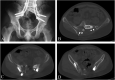

Background: Adequate margins are technically difficult to achieve for malignant tumors involving the sacroiliac joint due to limited accessibility and viewing window. In order to address the technical difficulties faced in iliosacral tumor resection, we proposed a technique for precise osteotomy, which involved the use of canulated screws and Gigli saw (CSGS) that facilitated directional control, anteroposterior linkage of resection points and adequate surgical margins. The purpose of the current study was to evaluate whether CSGS technique facilitated sagittal osteotomy at sacral side, and were adequate surgical margins achieved? Also functional and oncological outcomes was determined along with the noteworthy complications.

Methods: From April 2018 to November 2019, we retrospectively reviewed 15 patients who underwent resections for primary tumors of pelvis or sacrum necessitating iliosacral joint removal using the proposed CSGS technique. Chondrosarcoma was the most common diagnosis. The osteotomy site within sacrum was at ipsilateral ventral sacral foramina in 8 cases, midline of sacrum in 5 cases, and contralateral ventral sacral foramina and sacral ala with 1 case each. The average intraoperative blood loss was 3640 mL (range, 1200 and 6000 mL) with a mean operation duration of 7.4 hours (range, 5 to 12 hours). The mean follow-up was 23.0 months (range, 18 and 39 months) for alive patients.

Results: Surgical margins were wide in 12 patients (80%), wide-contaminated in 1 patient (6.7%), and marginal in 2 patients (13.3%). R0 resection was achieved in 12 (80%) patients and R1 resection in 3 patients. There were three local recurrences (20%) occurred at a mean time of 11 months postoperatively. No local recurrence was observed at sacral osteotomy. The overall one-year and three-year survival rate was 86.7% and 72.7% respectively.Complications occurred in three patients.

Conclusions: The current study demonstrated that CSGS technique for tumor resection within the sacrum and pelvis was feasible and can achieve ideal resection accuracies. The use of CSGS was associated with high likelihood of negative margin resections in the current series. Intraoperative use of CSGS appeared to be technically straightforward and allowed achievement of planned surgical margins. It is worthwhile to consider the use of CSGS technique in resection of pelvic tumors with sacral invasion and iliosacral tumors, however further follow-up at mid to long-term is warranted to observe local recurrence rate.